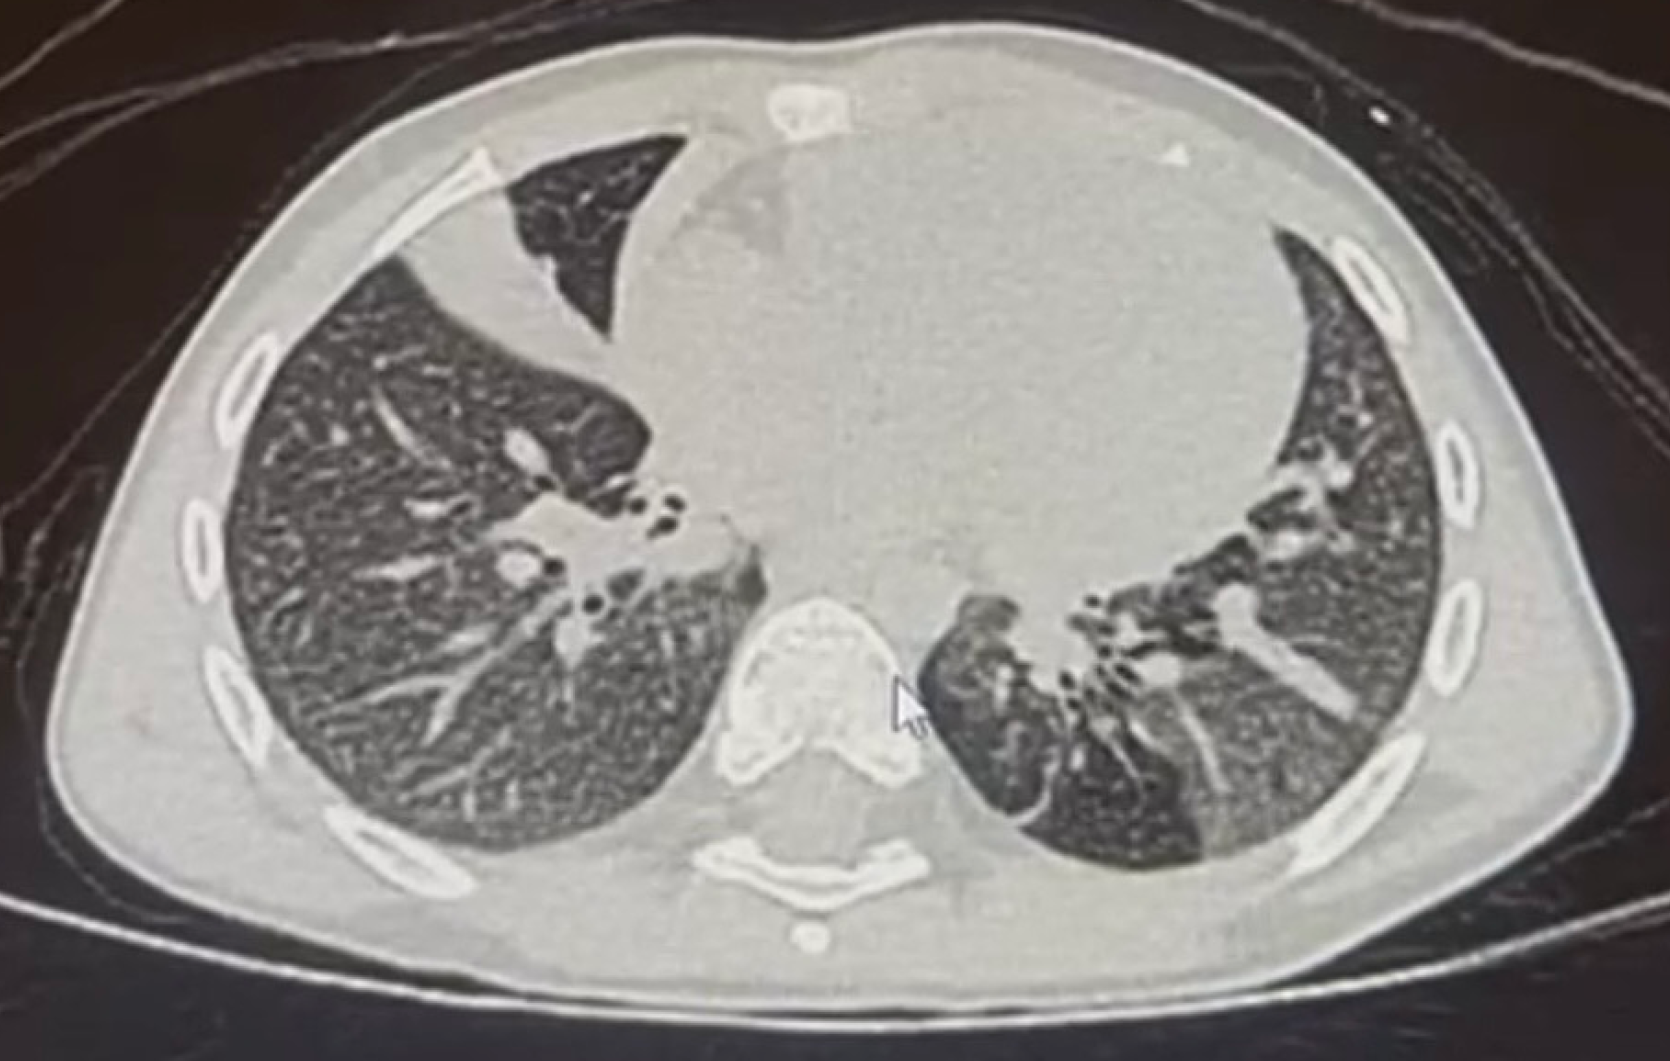

Figure 2 Chest high-resolution computed tomography scan of a patient with post-infectious bronchiolitis obliterans post adenovirus showing middle lobe atelectasis with air bronchogram and bronchiectasis.

Diffuse mosaic pattern and air trapping.